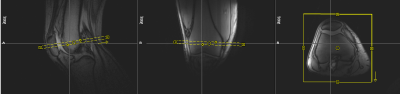

Figure 2: Slice setup for the dynamic MRI measurement.

Figure 3: MRI time frames from the middle of the a) baseline (t = 1 min), b) loading (t = 5 min) and c) unloading (t = 27 min) periods, respectively. The region of interest (ROI, yellow box) for the cartilage thickness evaluation was determined via a manually drawn line (blue) between the two outmost contact points of patellar and femoral cartilage, discarding the outer 20 % on each side. The mean distance between patellar and femoral bone-cartilage interfaces within this ROI was then measured perpendicular to this line.